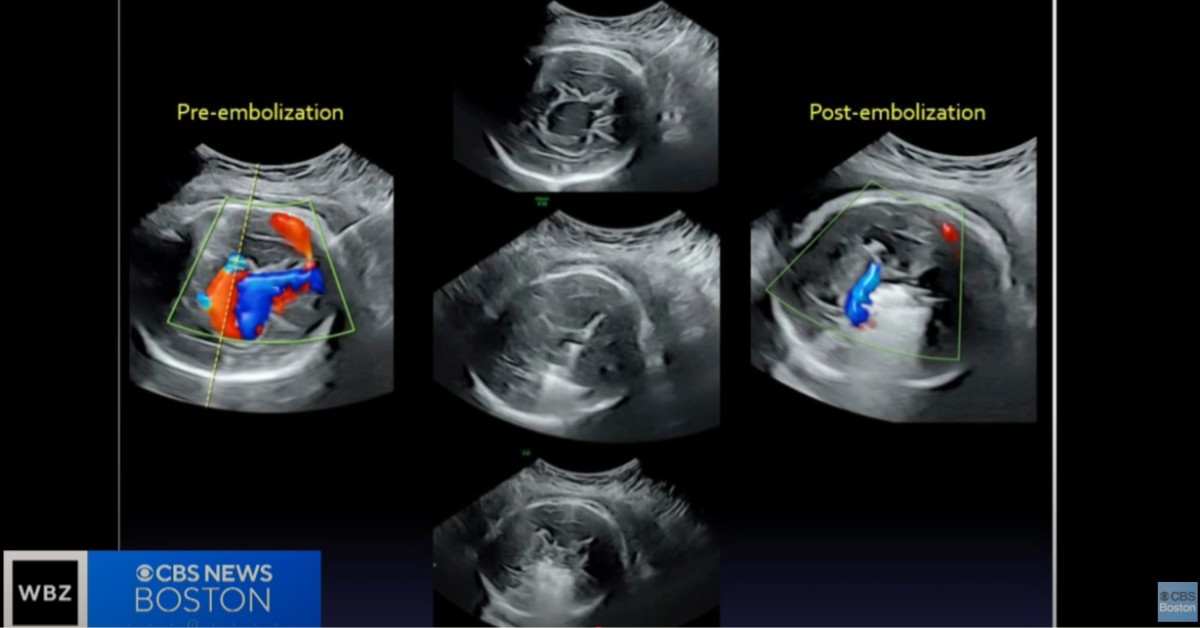

Malformacija Galenove vene je stanje koje uzrokuje nakupljanje krvi u džepu mozga, što može izazvati ozbiljne komplikacije poput oštećenja mozga, zatajenja srca, pa čak i smrt. Ovaj problem je prvi put primećen tokom rutinskog ultrazvuka u 30. nedelji trudnoće, a operacija je bila neophodna kako bi se sprečili potencijalni fatalni problemi.

Operacija je uključivala vrlo preciznu i složenu tehniku, u kojoj su lekari koristili ultrazvučno snimanje i iglu kako bi precizno ušli u mozak fetusa i postavili spirale koje bi blokirale krvnu žilu koja je izazivala problem.

Ova operacija pokazuje potencijal za lečenje teških fetalnih malformacija pre nego što dođe do komplikacija u postporođajnom periodu. Beba koja je podvrgnuta ovom zahvatu sada je zdrava, a njeno stanje je dobro. Lekari su bili u mogućnosti da normalizuju protok krvi u mozgu fetusa, što je sprečilo dalja oštećenja i omogućilo zdrav razvoj.